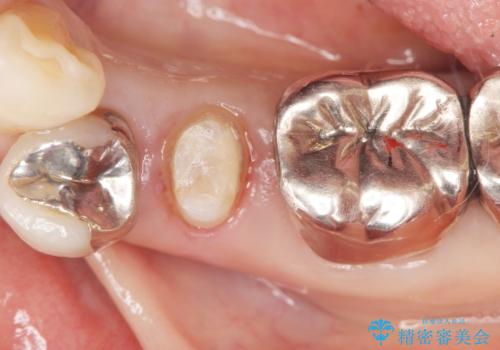

患者様のご希望により、セラミッククラウンにより可及的にう蝕除去後の補綴及び歯並びの改善を行いました。

セラミッククラウンの自然な仕上がりと咬み心地に大変ご満足頂けました。

歯がしみる症状もなくなり、外側に出ていた歯が気にならなくなったと喜んで下さいました。

クラウンの種類:オールセラミッククラウン エコノミー